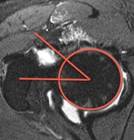

SCFE AI

SCFE Detection AI

Expert level detection of slipped capital femoral epiphysis using AI. 99% accurate.

A. Campion, A. Ha, B. Do, et al.